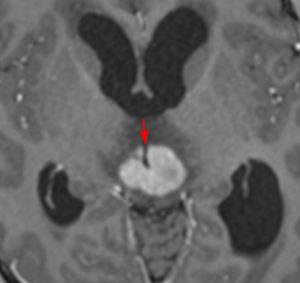

再発ジャーミノーマの画像です。延髄背側の閂 ovexという部位に再発しています。

このパターンはとても多いです。なぜかというと,全脳室照射の時に,第4脳室下端のovexの上衣 ependyum を照射野に入れない放射線治療医の先生がいるからです。放射線科の先生にもちょっとした知識が必要なのです。

これは再治療で腫瘍が消えても不可逆的な重症の延髄障害を残してしまいます。